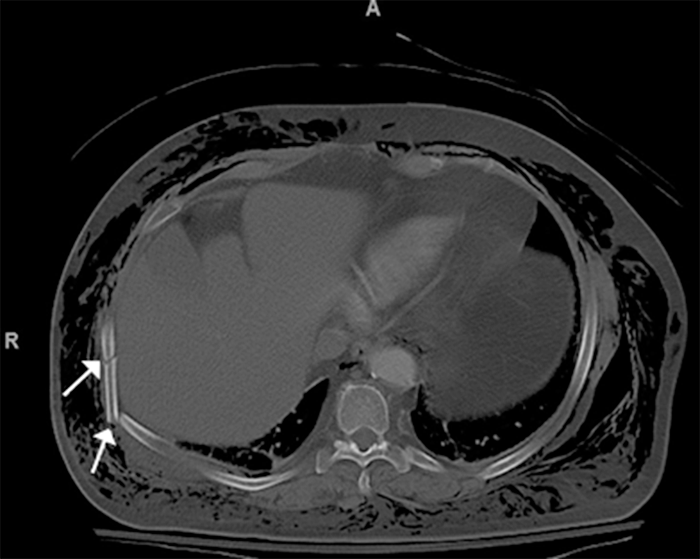

No significant pneumothorax was noted, but she had a large amount of subcutaneous emphysema (Figure 4). She also developed lateral herniation of the right lower lobe through the seventh and eighth rib space (Figure 5).

On arrival at our hospital, the patient had severe subcutaneous emphysema. She was hemodynamically normal, saturating 95% on a 3 L nasal cannula. Her imaging revealed comminuted and displaced fractures of right-sided ribs 7 through 9 (Figures 1, 2, and 3).

Figure 1. Comminuted Right Lateral Seventh Rib Fracture (white arrow). Published with Permission

Figure 2. Comminuted Right Posterior and Lateral 8th Rib Fracture (white arrow). Published with Permission

Figure 3. Comminuted Right Posterior 9th Rib Fracture (white arrow). Published with Permission